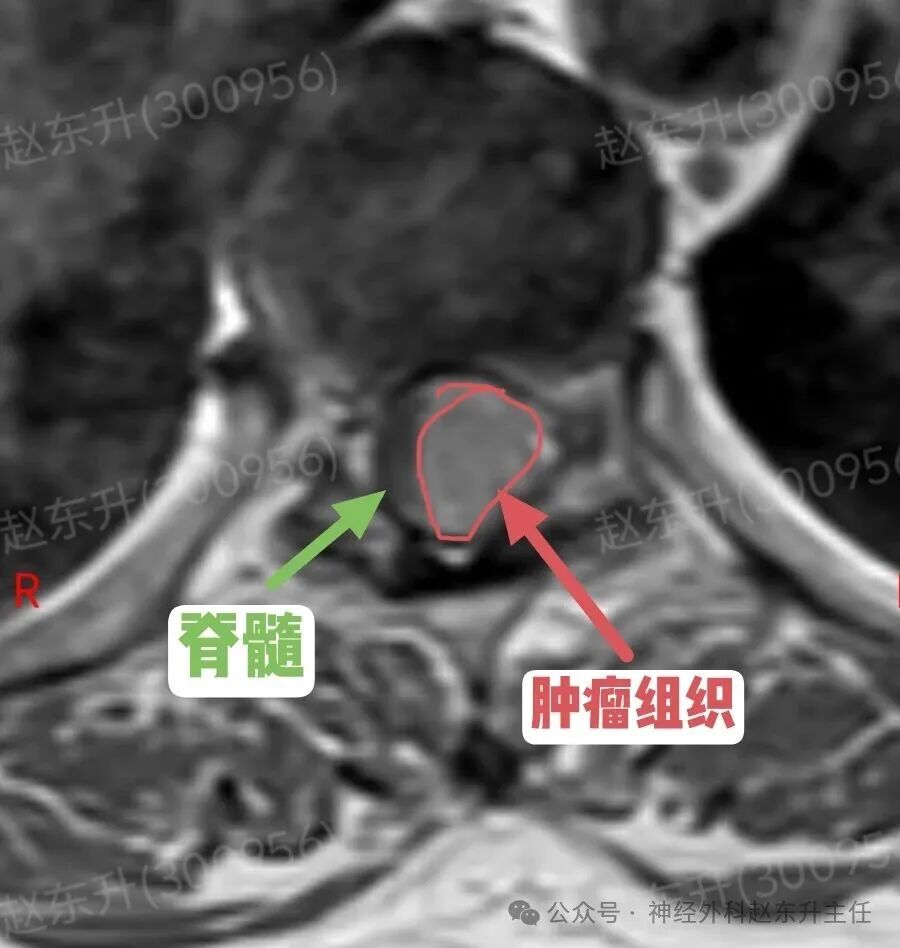

有一天门诊来了一位69岁的甘肃女性患者。因为长期腰腿疼,在多家医院就诊治疗无效,长期按摩针灸拔罐艾灸电疗磁疗腰腿疼,稍有缓解。随后又持续加重,在外院查腰椎磁共振,未见明显异常,随后在向上查胸椎磁共振,发现椎管内一个巨大肿瘤压迫脊髓比较明显。她疼痛评分有6分,夜间疼痛难忍,难以入睡。此次发现椎管肿瘤以后来到我院就医。根据胸椎磁共振的表现,考虑脊膜瘤可能。随后在全麻下,我们在显微镜下彻底切除了肿瘤组织术后患者疼痛缓解下地行走,较术前改善大小便也恢复正常了。

图片图片图片图片图片图片肌电图提示下肢神经、骶神经损伤术中切除的肿瘤组织西安市红会医院神经外科赵东升主任介绍:椎管内脊膜瘤是一种常见的、通常为良性的椎管内肿瘤,起源于覆盖脊髓和神经根的脊膜(特别是蛛网膜的“帽细胞”)。核心特征:性质:绝大多数(90%以上)为良性(WHO I级),生长缓慢。位置:可发生于椎管的任何节段,但最常见于胸椎(约占70%),其次是颈椎、腰椎少见。特点:肿瘤通常有完整的包膜,与硬脊膜基底紧密相连,像一颗“附着在墙壁上的珍珠”,可压迫脊髓和神经根,但通常不侵入神经组织本身。发病率:是椎管内最常见的肿瘤之一,约占所有椎管肿瘤的25%。好发于中年女性(女:男比例约为4:1),可能与激素水平有关。

病史与神经系统查体:医生通过询问病史和详细的神经系统检查,初步判断病变的节段和严重程度。影像学检查(确诊的关键):增强磁共振(MRI): 是诊断的金标准。典型表现:T1加权像上呈等或稍低信号,T2加权像上呈等或稍高信号;增强扫描后呈现显著的、均匀的强化。特征性的“硬脊膜尾征”(肿瘤附着处硬脊膜线状强化)具有重要诊断价值。可清晰显示肿瘤与脊髓、神经根的关系。CT扫描:可显示肿瘤是否伴有钙化(沙粒体型脊膜瘤常见),以及是否有椎体或椎弓根的骨质增生,但对软组织分辨率不如MRI。X线平片:作用有限,可能仅见椎弓根间距增宽等间接征象。